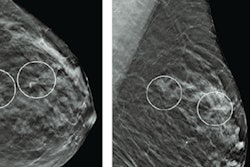

Radiologists saw an improvement after switching from computer-aided detection (CAD) to artificial intelligence (AI) to analyze digital breast tomosynthesis (DBT) screening exams, according to a talk at the Society of Breast Imaging/American College of Radiology symposium.

In the first period (September 1, 2019, to August 31, 2020), the radiologists used CAD-enhanced synthetic 2D views on PowerLook Tomo Detection software (iCAD) concurrently during interpretation of DBT exams. The second time period (January 1, 2020, to December 31, 2020) occurred after adoption of concurrent use of version 2.6 of ProFound AI (iCAD) deep learning-based software, which provides lesion outlines, lesion scores, and an overall case score.

All DBT exams were performed on a Senographe Pristina system (GE Healthcare). The researchers calculated the average cancer detection rate, abnormal interpretation rate, positive predictive value for cancer screenings with abnormal interpretations (PPV1), and positive predictive value of biopsies performed (PPV3).